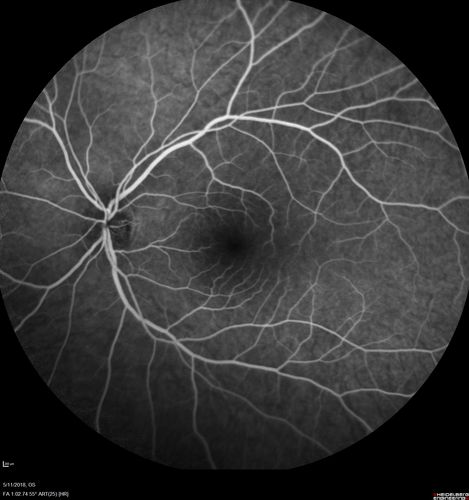

Multifocal Choroiditis - Pneumocystis - aspergillis - cryptococcus

31 year old male with anaplastic astrocytoma on chemotherapy with mild vision loss in the right eye.  LP did not reveal organism.  He was placed on a trial of anti-fungal medications and lost to follow-up